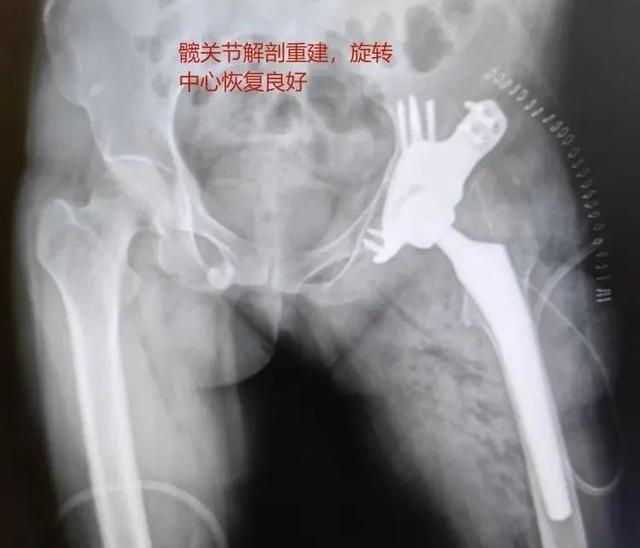

5. 术后复查

术后,患者旋转中心恢复良好。